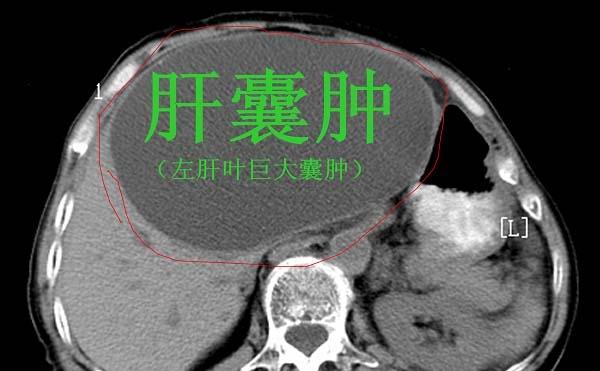

第一,肝囊肿

肝囊肿是最常见肝脏结节,肝囊肿的原因并不是特别的清楚。简单来说,肝囊肿就是肝里面有一个包块,包块里面是水。肝囊肿可以是单发的,也可以是多发的。如果肝囊肿没有症状,直径小于5厘米,不需要处理,定期复查即可。如果肝囊肿不断变大,出现不舒服,压迫周围组织,可以做手术。现在肝囊肿一般都是微创手术,腹腔镜下开窗引流,把囊液引出来就可以了,但是肝囊肿容易复发。还有一种遗传性疾病,肝脏和肾脏多发的囊肿,肝上面有十几个甚至几十个囊肿。对于这样的患者,平时一定要定期复查,注意保护肝功能,因为后期可能出现肝衰竭,甚至要做肝移植手术。